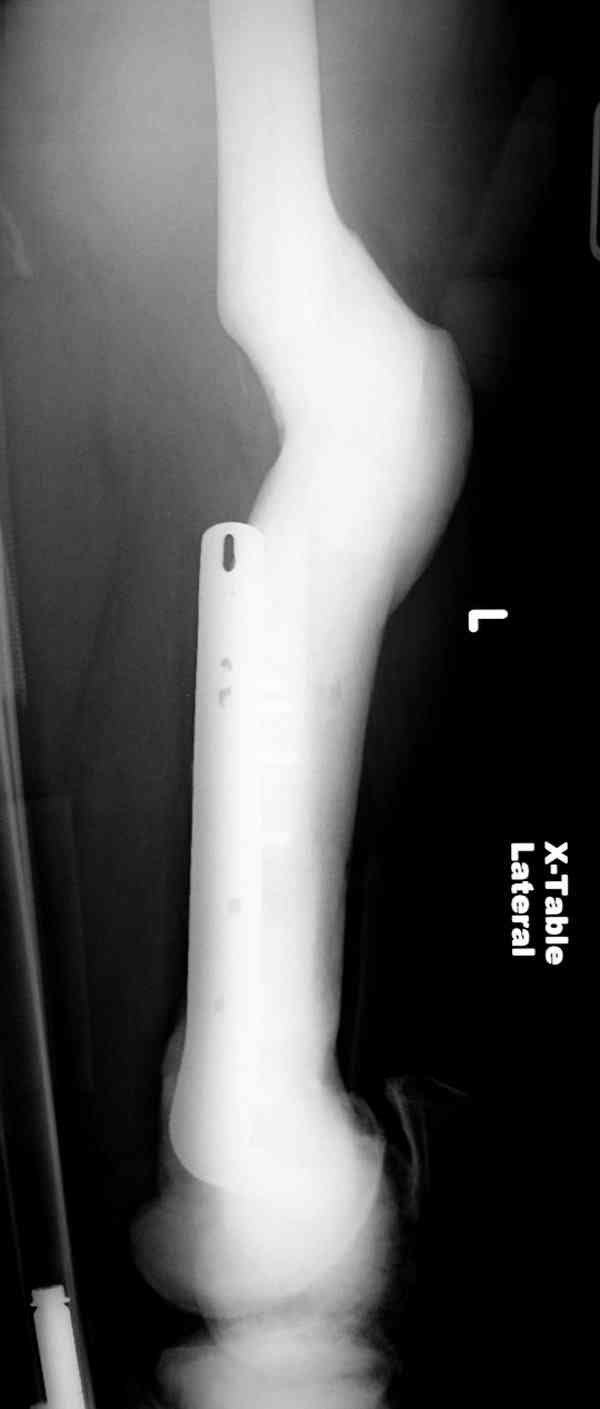

Остеопетроз характеризуется болями в костях, а на ренгене следы множественных несращении длинных трубчатых костей и “белая-мелоподобная” кость.

“При лечении переломов у больных с остеопетрозом (в прошлом году был случай) необходимо быть готовым к длительным операциям из-за трудности

обработки традиционными методами "мраморной" кости, иметь в наличие достаточное количество свежих острых инстументов и персонала при необходимости замены (были случаи отстрочки операции на следующий день из-за физической усталости персонала), и надо избежать особо трудоемких операции как интрамедуллярное сверление”.

слайды из прошлегодного случая.